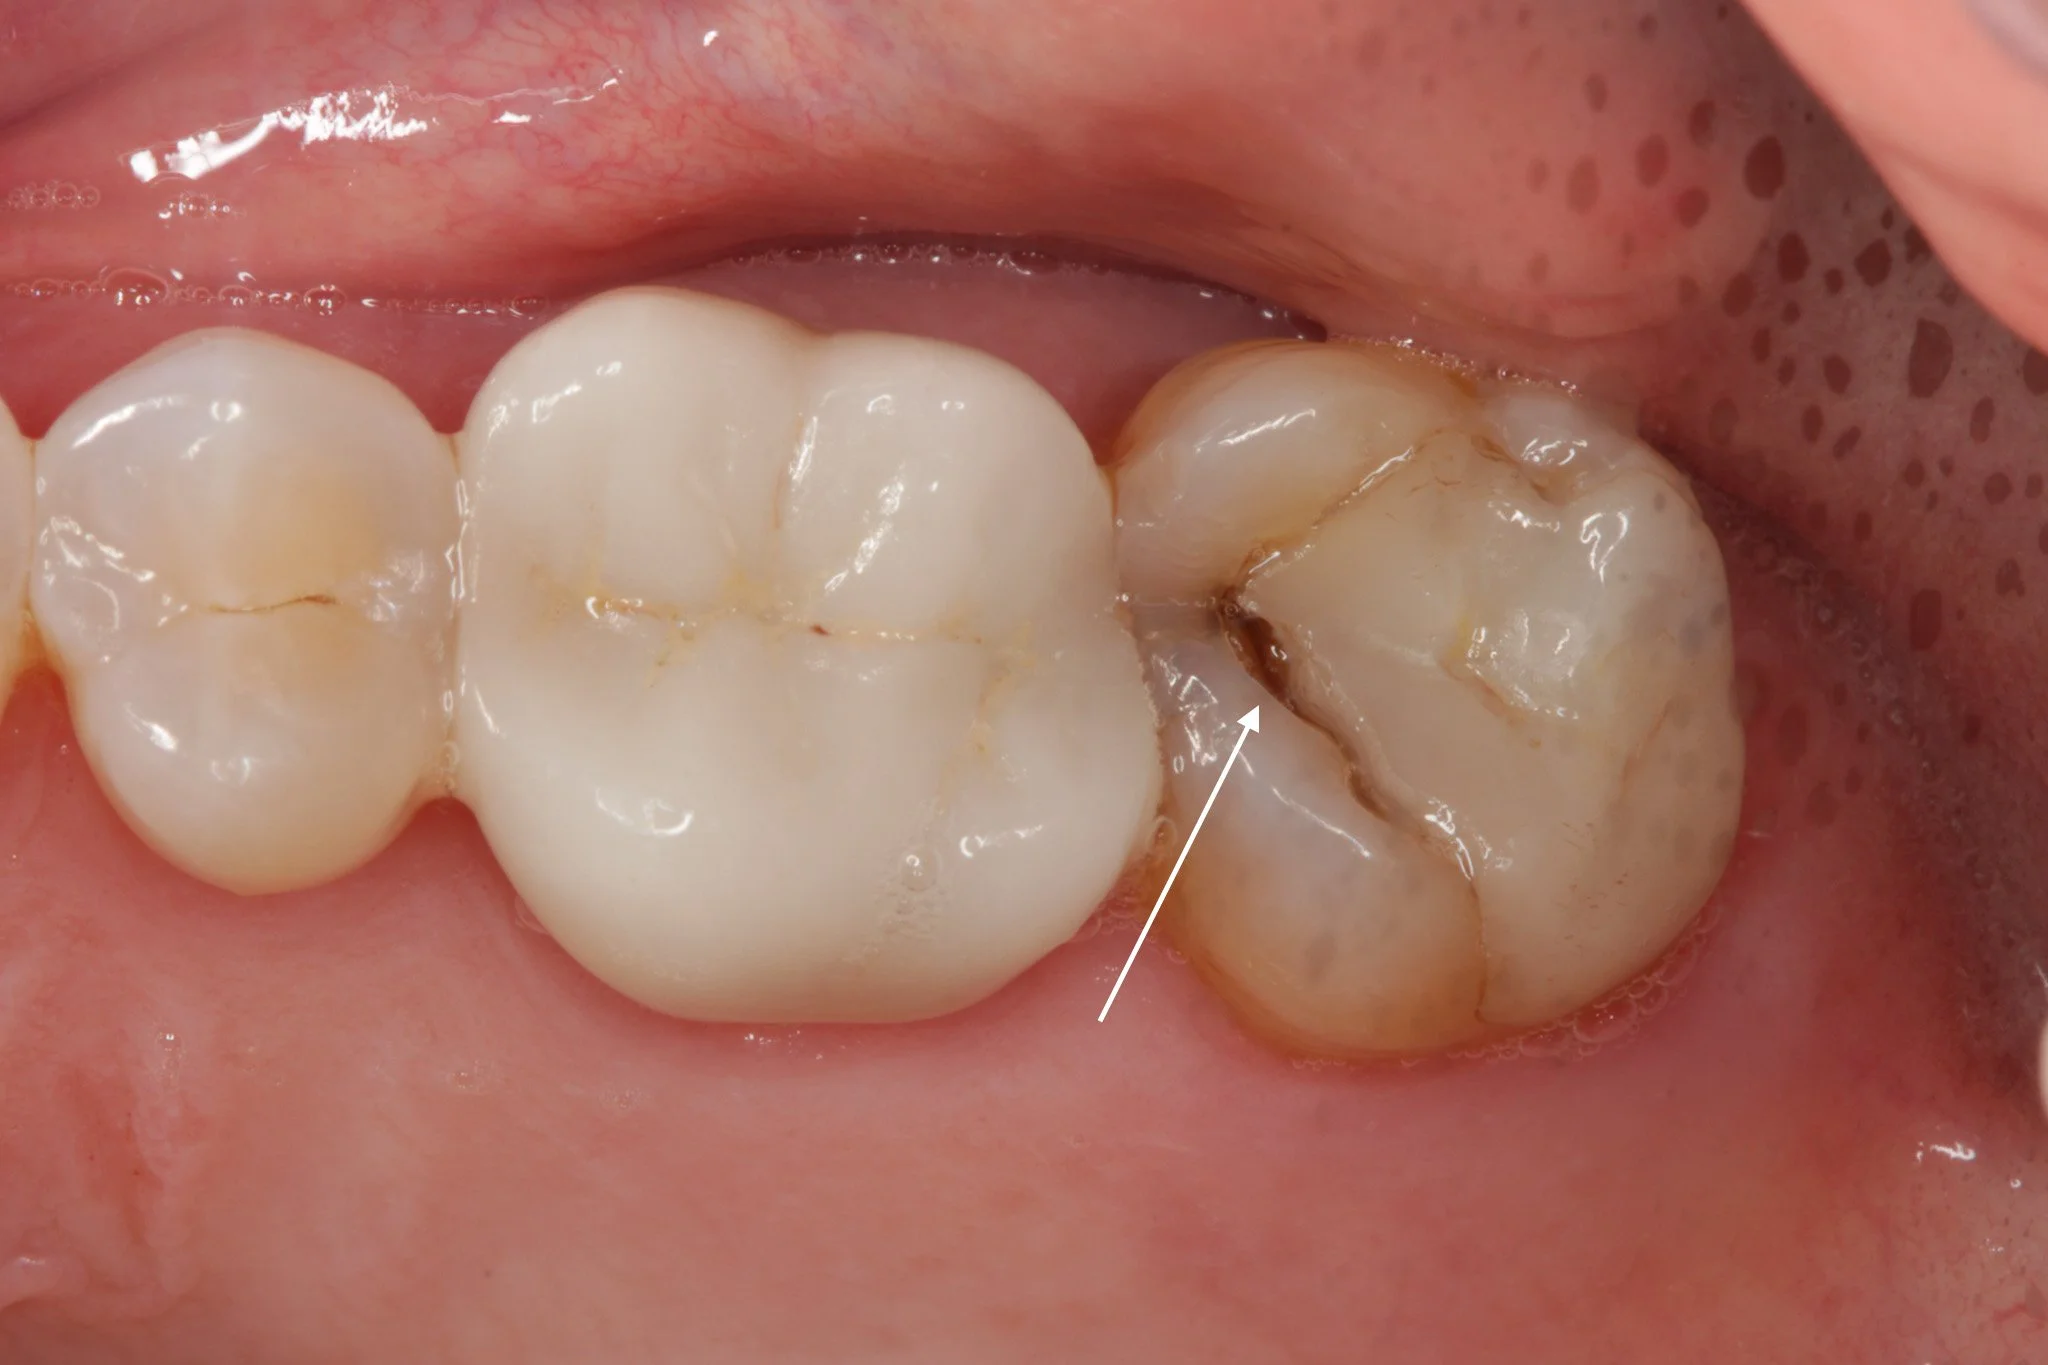

A broken filling, left untreated and now the tooth has fractured

There is a gap at the amrgin where the fillings meets the tooth, allowing bacteria to gather and decay the tooth underneath